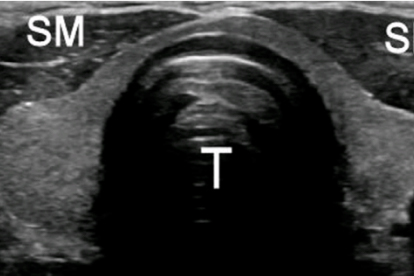

甲状腺囊肿是常见的甲状腺疾病之一,多由甲状腺结节囊性变或先天性发育异常引起。早期诊断和规范治疗对预后至关重要,选择专业医疗机构就诊有助于获得准确诊断和有效治疗。

甲状腺囊肿患者日常应注意定期复查,监测囊肿变化。饮食上保证适量碘摄入,避免过量食用海带、紫菜等高碘食物。保持规律作息,避免过度疲劳。如发现颈部肿块突然增大、出现疼痛或压迫症状,应及时就医。超声检查是监测甲状腺囊肿有效的方法,建议每6-12个月复查一次。对于接受治疗的患者,应遵医嘱按时服药和复查,不要自行调整治疗方案。